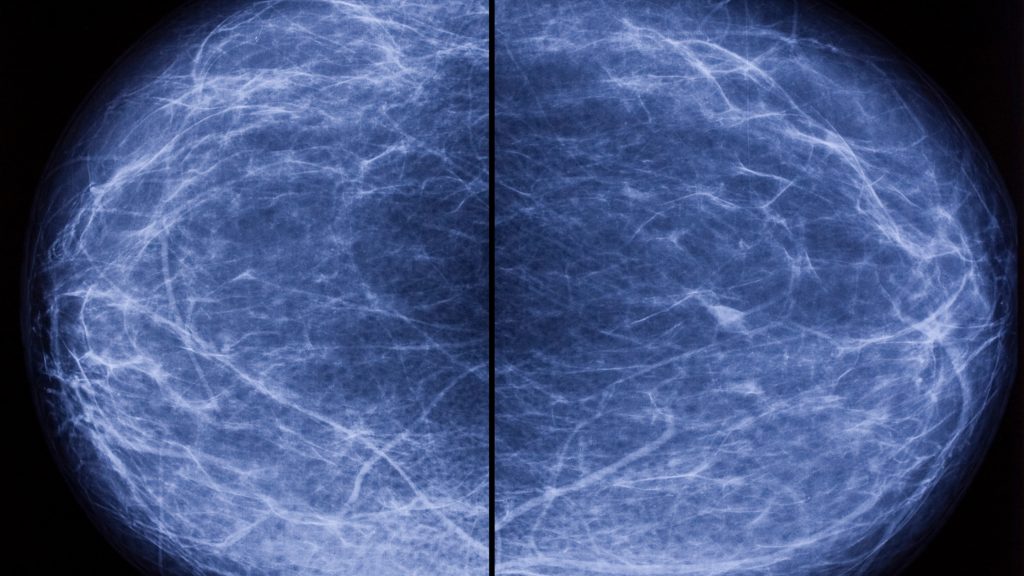

In a typical mammogram, doctors are looking for abnormalities that could signal breast cancer, such as suspicious lumps, masses or small calcium deposits. While they are performing the assessment, they also make note of your breast density.

Breast tissue is composed of glandular and fibrous tissues, which appear white on a mammogram, as well as fat, which appears black. Having dense breasts means you have more of the white tissue, making it more difficult for doctors to detect breast cancer. Having dense breasts has nothing to do with size or shape, but some risk factors include genetics, age, BMI, pregnancy and breastfeeding and the use of hormone replacement therapy.

The only way to determine your breast density is via mammogram interpreted by a radiologist. You will likely be notified by your provider following your routine mammogram.